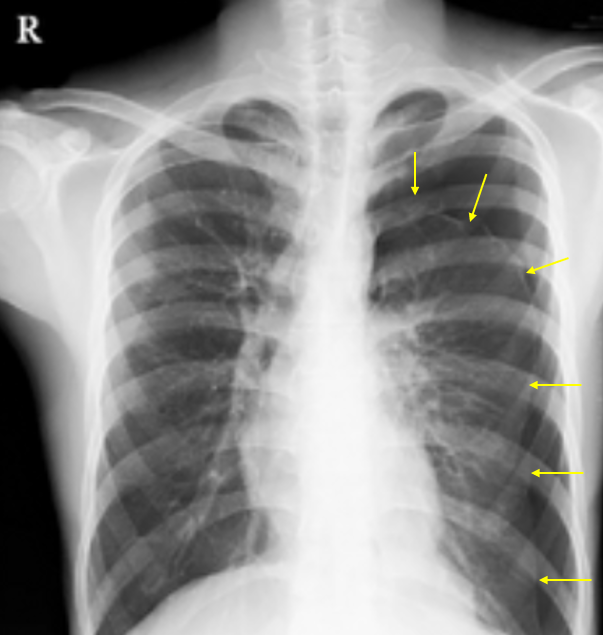

29세 남자가 1시간 전부터 숨이 찬다며 병원에 왔다. 태권도 사범으로 2시간 전 시범을 보이면서 기합을 지른 후 왼쪽 가슴이 뜨끔거리는 통증을 느꼈다. 병원에 와서는 숨이 차서 한 문장을 쉬지 않고 끝까지 말하지 못했다. 혈압 110/80mmHg, 맥박 110회/분, 호흡 28회/분, 체온 36.5℃이다. 청진에서 왼쪽 가슴의 호흡음이 잘 들리지 않고 타진에서 과공명이 있다. 가슴 X선 사진이다. 치료는?

Img | CXR: 좌측 폐 pleural line |

• CXR에서 좌측 폐에 pleural line이 보이며 distal하게 vascular marking이 없으므로 기흉으로 진단하며, 환자가 젊고 특이 병력이 없으므로 PSP로 진단할 수 있다.